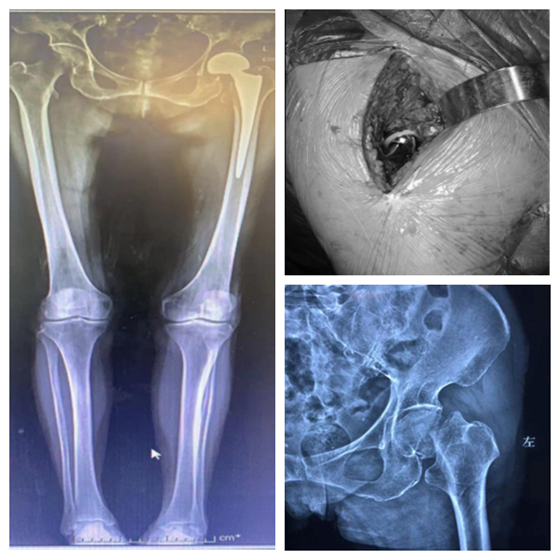

患者:罗某,86岁

患者:曹某,78岁

患者:王某,102岁

湘雅常德医院开院以来,主要收治的髋部骨折患者年龄从70-102岁不等,且多伴有心肺功能不全,合并多种内科疾患,具有手术风险高、难度大的特点。在科主任张朝跃主任医师和创伤组长王穗源副主任医师的带领下,与全院各临床科室、麻醉、手术部进行多学科合作,开展了一系列针对高龄及超高龄患者的髋部骨折个性化手术治疗,术后2-3天即可扶助下地行走,患者及家属满意度极高,极大地减轻了老年患者的痛苦,延长了患者的生命,减轻了家庭护理负担,获得了良好的社会口碑。